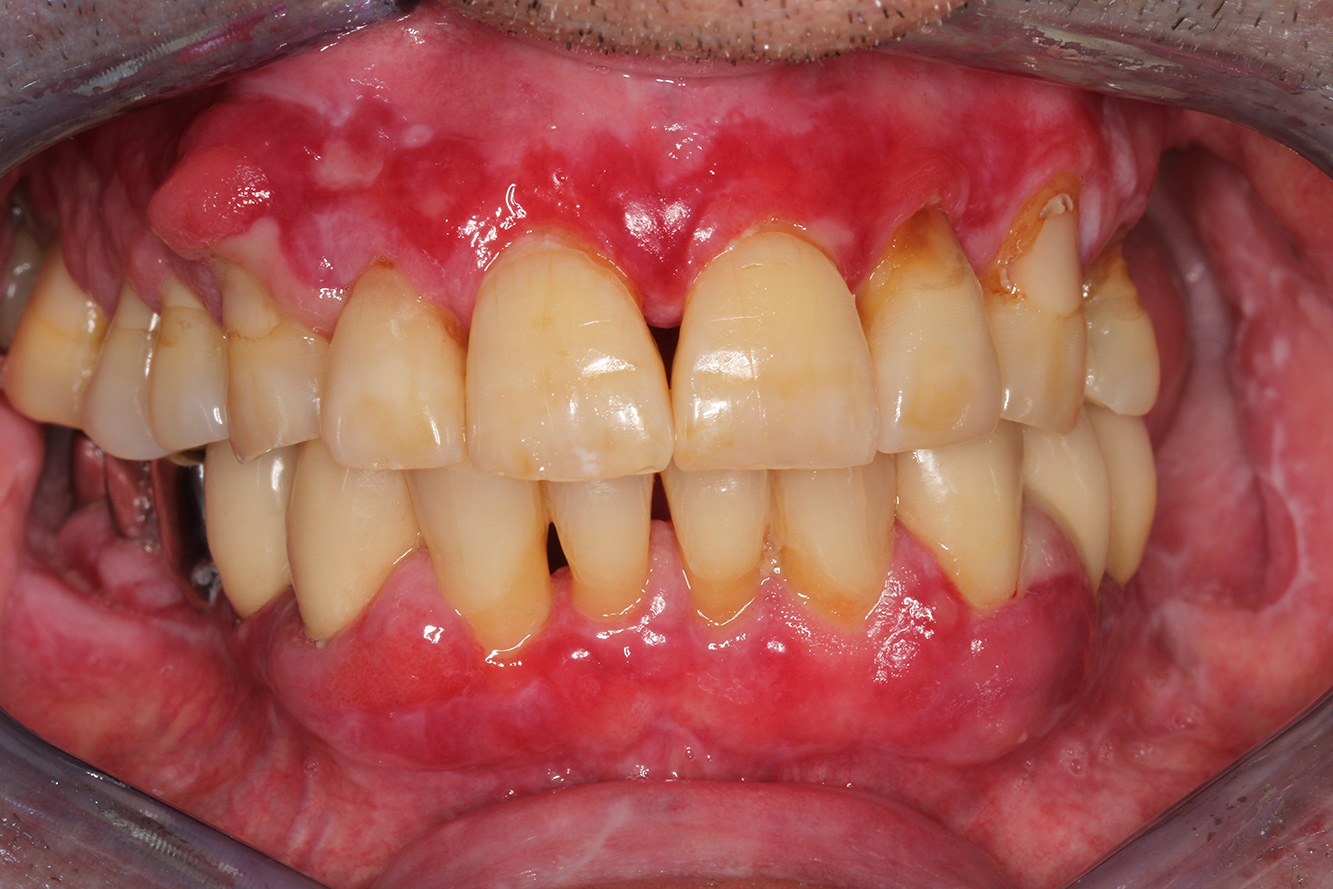

Se presenta un paciente de 71 años con trasplante de riñón e hipertensión (presión arterial alta). Debido a su historia médica, es necesario el tratamiento continuo con ciclosporina para suprimir el sistema inmunitario y amlopidina para bajar la presión arterial. Además, el paciente relata encías sensibles y sangrantes. Desde el punto de vista de la salud oral, hay dientes restaurados con ocho piezas faltantes, hiperplasia gingival pronunciada, periodontitis en fase II, de grado B con bolsas activas y una caries inicial en la pieza 22. En la evaluación del riesgo de caries se ha establecido un riesgo de caries medio (API 60). Para la sesión de profilaxis se hacen las siguientes recomendaciones.

Con base en la historia médica, se detecta un riesgo de complicaciones importante. Debido al trasplante de riñón, el paciente está inmunodeprimido (ciclosporina), también tiene el sistema inmunitario debilitado y necesita profilaxis para infecciones (recomendación: 2 g de amoxicilina como antibiótico 1 h antes de la sesión). Al mismo tiempo, el tratamiento continuo hace que el paciente tenga un mayor riesgo de enfermedad, dado que la hiperplasia gingival establecida está asociada a la medicación (20).

Se debe abordar la situación del paciente, especialmente cuando se trata de motivación y aprendizaje. La hiperplasia gingival dificulta la higiene oral en casa. La mayor susceptibilidad a las infecciones y el progreso y la nueva formación de hiperplasias (22) debe hablarse de igual a igual. Al mismo tiempo, deben explicarse las técnicas de higiene adecuadas según las necesidades individuales.

No hay recomendaciones específicas para la limpieza. Según el grado de conocimiento, debe hacerse el pulido rotativo de forma selectiva en zonas sensibles a la erosión. Precisamente porque la salud oral del paciente es frágil, es importante crear las mejores condiciones posibles para el mantenimiento en casa en la sesión de profilaxis, por ejemplo, creando superficies lisas, fluorizando para prevenir las caries y con enjuague bucal con clorhexidina para las inflamaciones activas.

Para el paciente se recomienda un intervalo de control posterior más corto, de tres a cuatro meses. Esto se debe principalmente a la hiperplasia gingival asociada a la medicación, la situación de cuidado difícil asociada y el alto riesgo de progresión de la periodontitis.